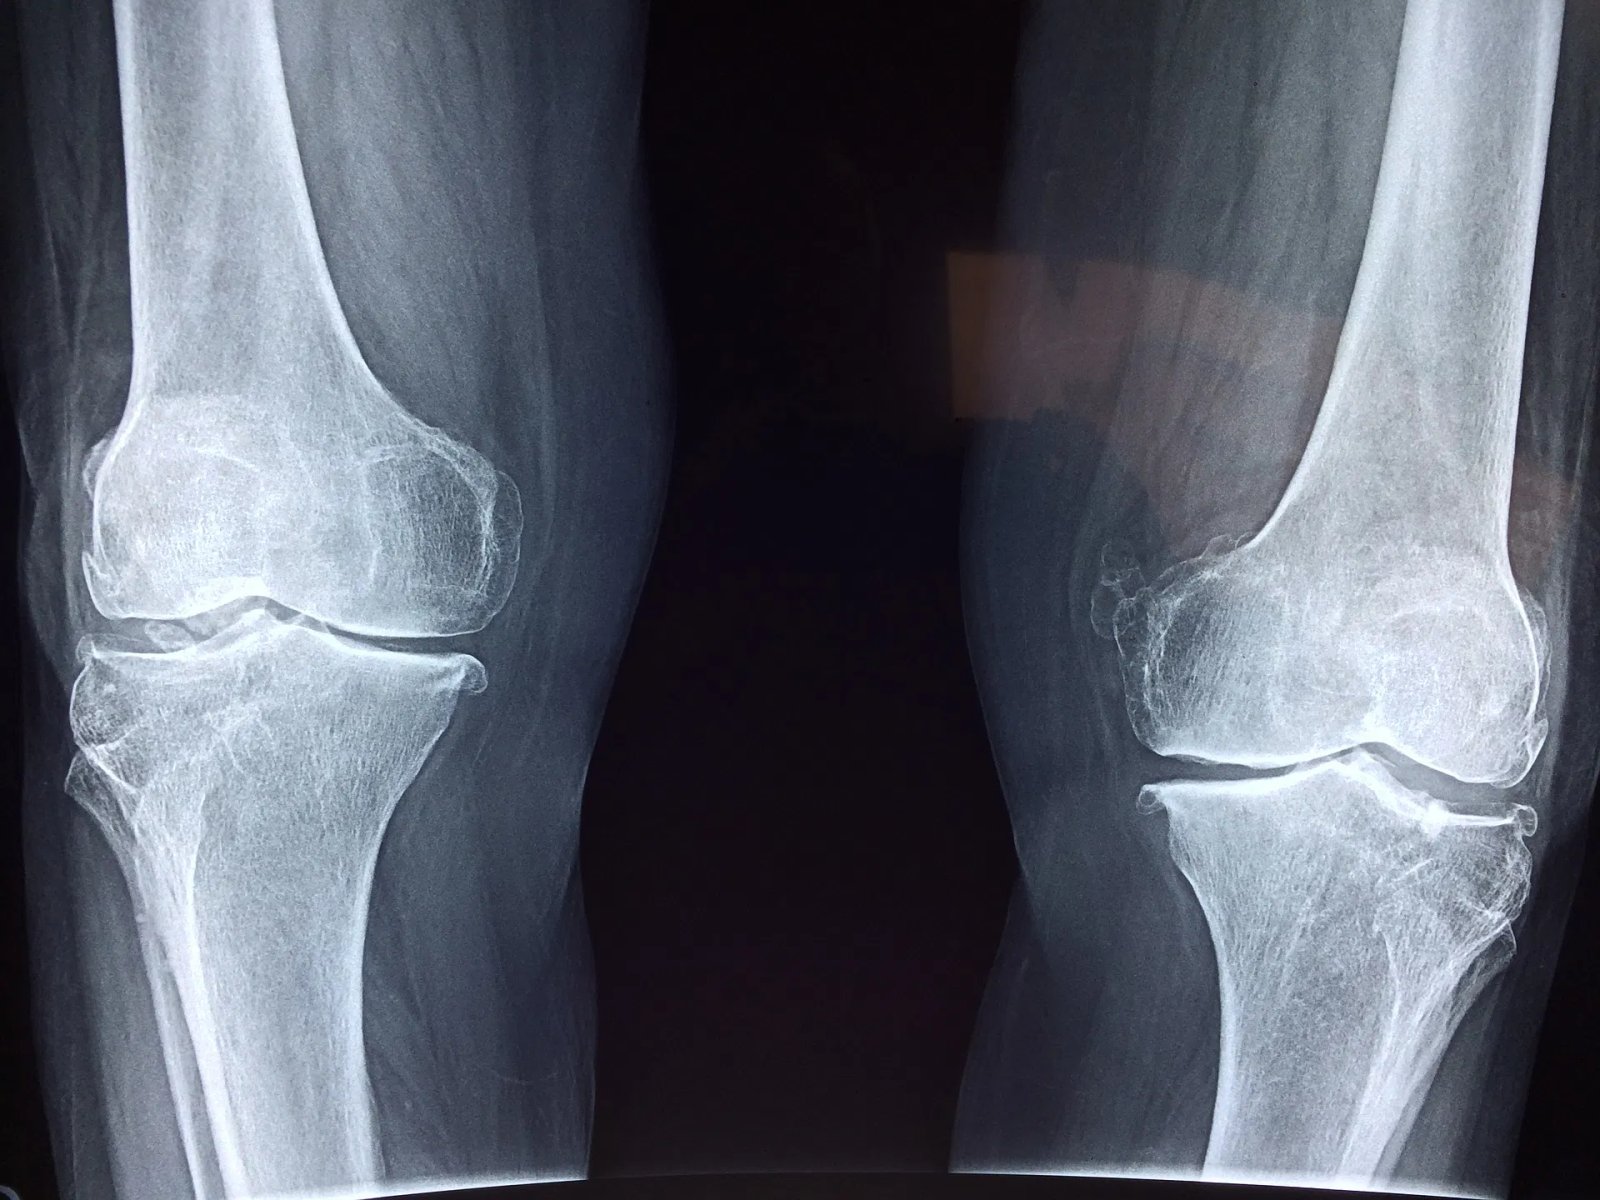

Osteoporosis Management

Osteoporosis is quite common among Indian population. Osteoporosis increases fracture risk.

At SOH we aim to identify patients at risk of osteoporosis, ensure early diagnosis and optimisation of treatment.